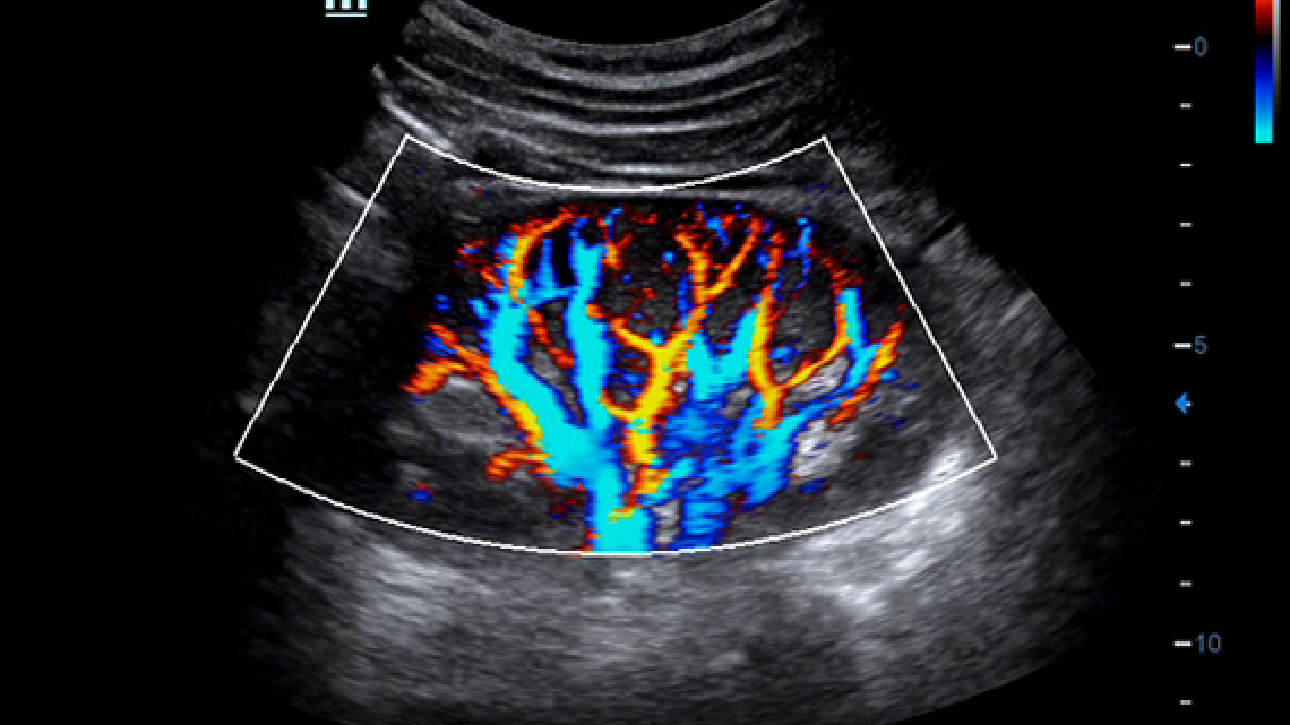

Clinical Images